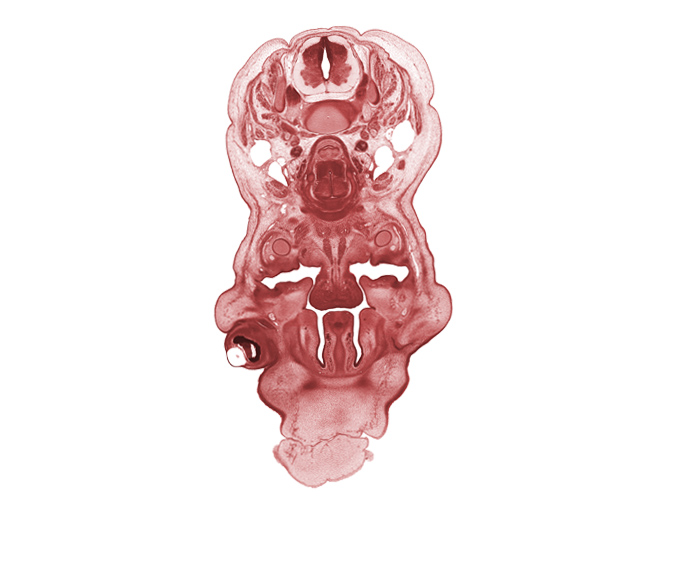

Carnegie Embryo #4090 | Location: 12-7

Keywords: C-5 spinal nerve, anterior spinal vessels, head mesenchyme, inferior meatus, inferior nasal concha, internal jugular vein, interorbital ligament, jugular lymph sac, mandible, nasal cavity (nasal sac), oral cavity, palatine shelf, pharyngeal endoderm, platysma muscle, spinal accessory nerve (CN XI), sternocleidomastoid muscle, subarachnoid space, trapezius muscle

Source: The Virtual Human Embryo.